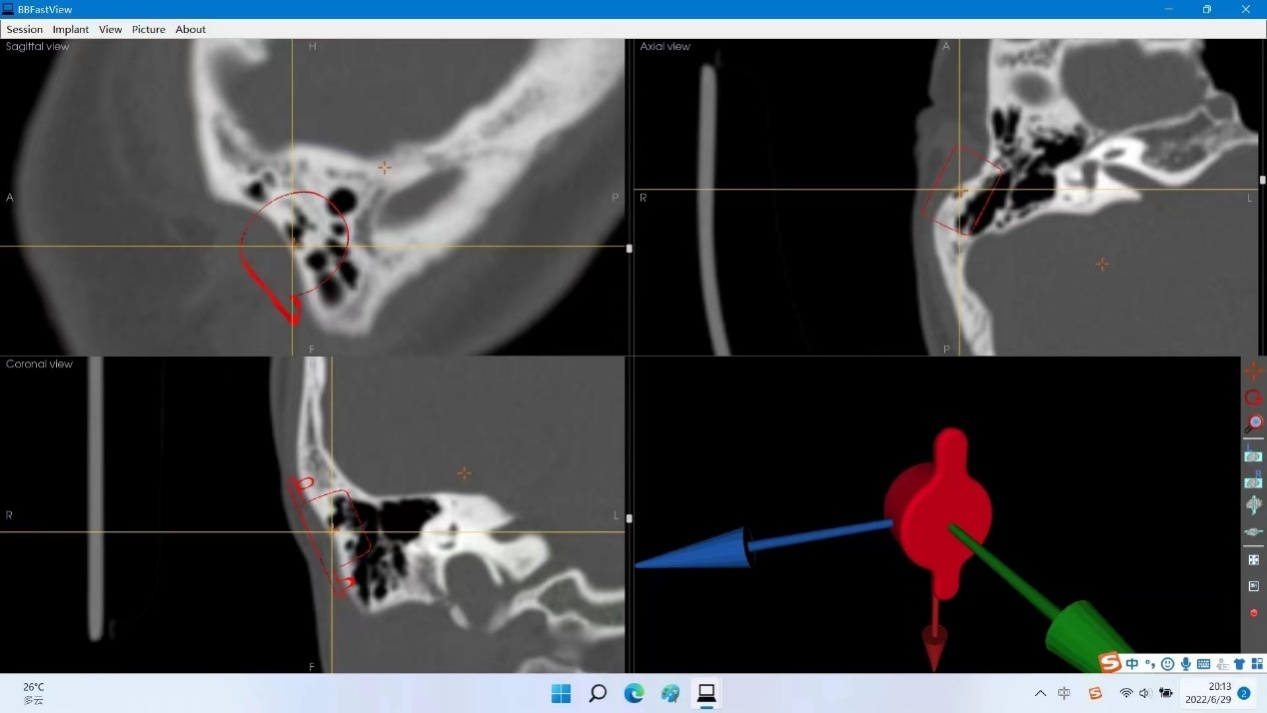

(根据患者颅骨薄层CT三维重建后确定的最佳骨桥基座植入点)